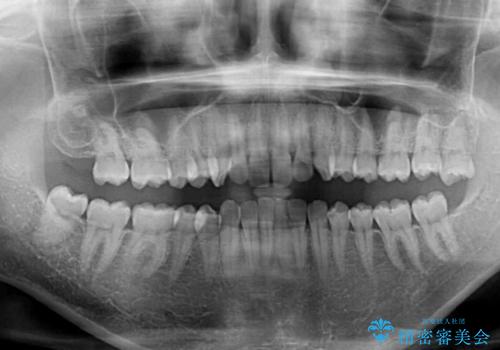

- 深い咬み合わせ(ディープバイト)と前歯のデコボコを気にして来院された患者様です。

インビザラインによる上下歯列の側方拡大と後方移動、IPR(歯と歯の間を削る)にるスペースの獲得により、デコボコとディープバイトを改善することとしました。

後方移動に際し、下顎の親知らずは2本とも抜歯することとしました。